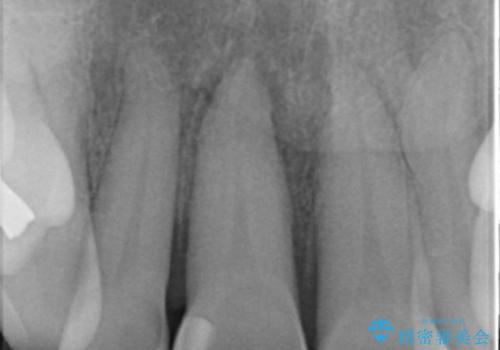

- 転んで前歯が折れたとのことで来院されました。

検査の結果、歯は大きく折れておらず、骨の中に埋め込まれていた状態であったため、部分矯正で歯を引っ張り出していきます。

ぶつけて埋まってしまった歯は、場合によって矯正治療で引っ張り出すことで保存することができます。

今回は歯の神経が死んでしまっていたため、根管治療後に被せ物を装着して見た目の綺麗さを回復しました。